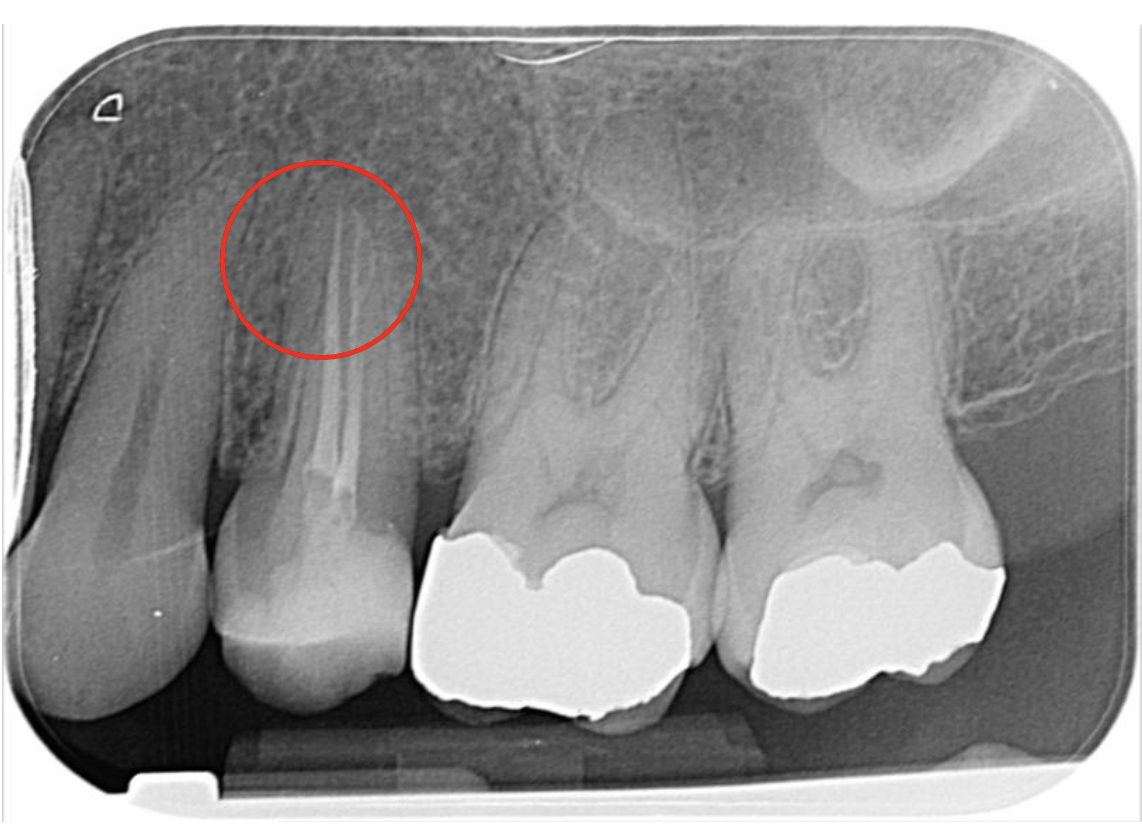

This upper second premolar Vertucci type 4 case was diagnosed with SIP and no clear apical change on IOPA.

It was prepared using 1403, 2004 and 2504 VS Flexi files from Toothsaver, as the canals appeared narrow and calcified on the pre-op IOPA. It was obturated with Onefill BC sealer and hydraulic condensation. On the post-op radiograph, you can see how the sealer-based obturation has filled the apical bifurcation of the buccal canal really nicely, which should help to achieve a positive outcome.